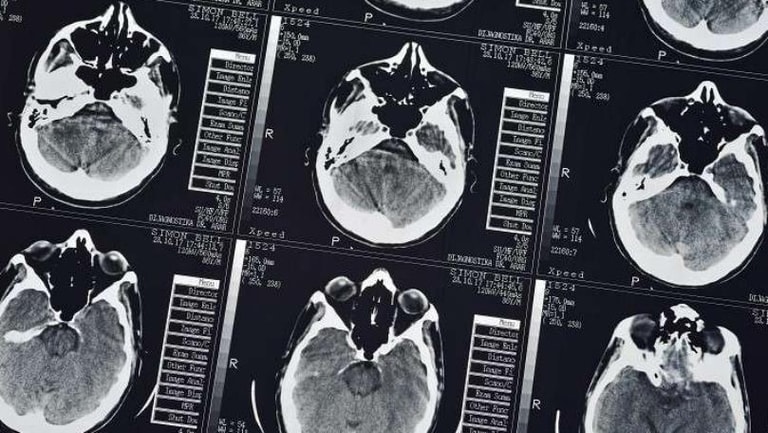

ولد طفل بريطاني وحجم دماغه يعادل 2% من الحجم الطبيعي، ولكن بفضل جهود والديه والأطباء، بقي على قيد الحياة ونما دماغه تقريبا إلى الحجم الطبيعي خلال 6 سنوات.

وبفضل الطرق الخاصة المستخدمة والتمارين اليومية، تعلم نوح الجلوس بنفسه وبدأ يحاول ركوب الموج، وعند بلوغه الثالثة من العمر نما حجم دماغه إلى 80% من الحجم الطبيعي. والآن ينوي تعلم السير بنفسه والاستمرار في رياضة ركوب الموج.